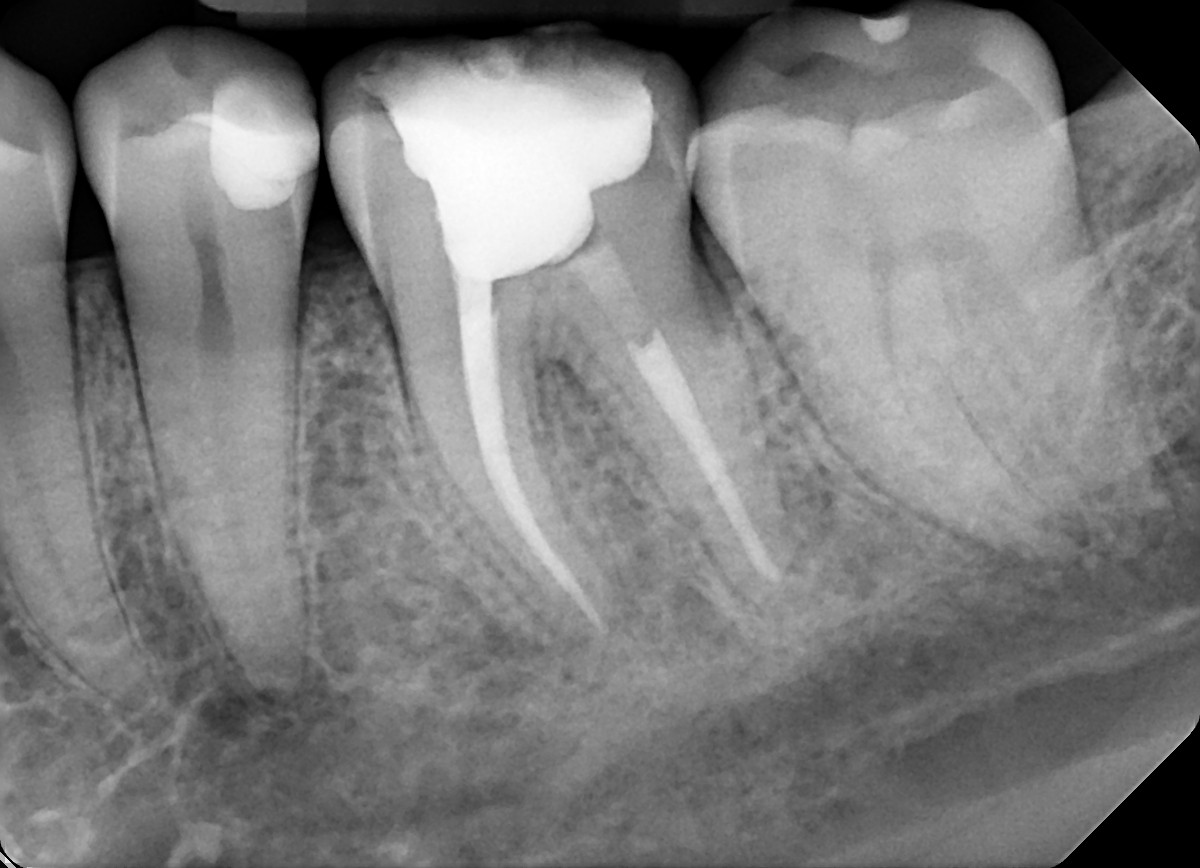

3. What option can describe the post placement in the X ray bellow for the tooth # 3.6?